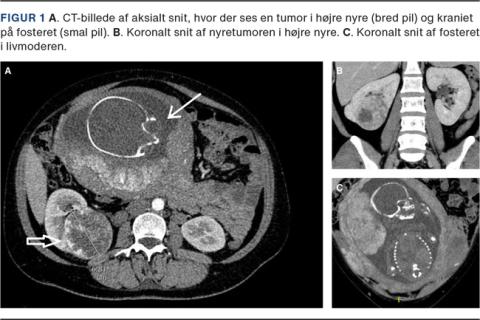

En 43-årig kvinde, som var diagnosticeret med hypertension og tidligere ryger, fik som tredjegangsgravid flere episoder med uspecifikke smerter og gener fra lænd og abdomen. Der blev påvist proteinuri, hvorfor hun i gestationsuge 25 + 0 blev UL-skannet pga. mistanke om nefrotisk syndrom. Skanningen viste en malignitetssuspekt tumormasse på højre nyre, og ved biopsi påvistes nyrecancer af typen clear cell RCC (ccRCC). Patienten blev henvist til en urologisk afdeling, hvor der efter konference mellem radiologisk, urologisk og obstetrisk afdeling blev udført CT af thorax og abdomen Patienten var på daværende tidspunkt i gestationsuge 29 + 6. CT viste ingen tegn til disseminering, men en 7 cm centralt beliggende tumor i højre nyre (Figur 1). Renografi vistenormal funktionsfordeling. Patienten blev tilbudt sectio og åben partiel nefrektomi som joint-venture mellem obstetrisk afdeling og urologisk afdeling, da hun var i gestationsuge 32 + 0. Indgrebet blev foretaget ved midtlinjeincision i epiduralanæstesi, indtil barnet var blevet forløst, hvorefter patienten blev lagt i generel anæstesi. Barnet var velskabt og kunne udskrives efter en kortere indlæggelse på neonatalafdelingen.

Endelig histologi bekræftede, at det drejede sig om ccRCC, T1b, Leibovich score 3. Efter halvandet år har der ikke været tegn til recidiv.